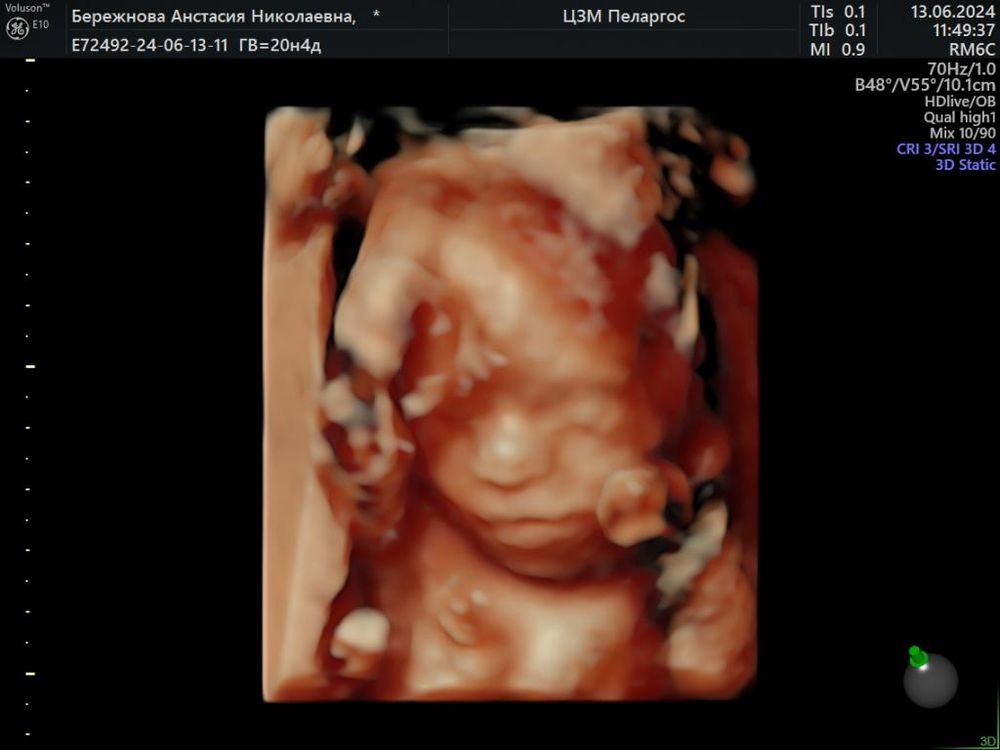

Как быстро прошли эти 22 недели.... Сходили на 2 скрининг все хорошо слава богу. 4 ребёнок очень охото чтобы был похож на меня)))

у нас похож на мужа, по крайней мере я здесь вижу его черты лица.. а вы на своём ничего не узнаёте?😄

Милая, мне кажется на меня но муж говорит что к сожелению у меня слабые гены и все дети его копия 😭😁😁😁